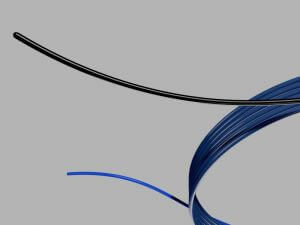

Bloomington, Ind.— Cook Medical announced the introduction of a two-in-one wire guide, the Motion™ Hybrid Wire Guide. This wire guide combines the features of a nitinol access wire guide and a Teflon™ fixed core wire guide into a single device.

The Motion wire guide is designed to provide access and control during a procedure with one wire. The Motion wire guide’s kink-resistant nitinol core and the flexible nitinol tip with hydrophilic coating facilitate the placement of the wire guide in order to establish access. The body of the Motion wire guide is Teflon-coated and constructed of tightly-wound stainless steel to help enable the passage of instruments and to provide control during the procedure.